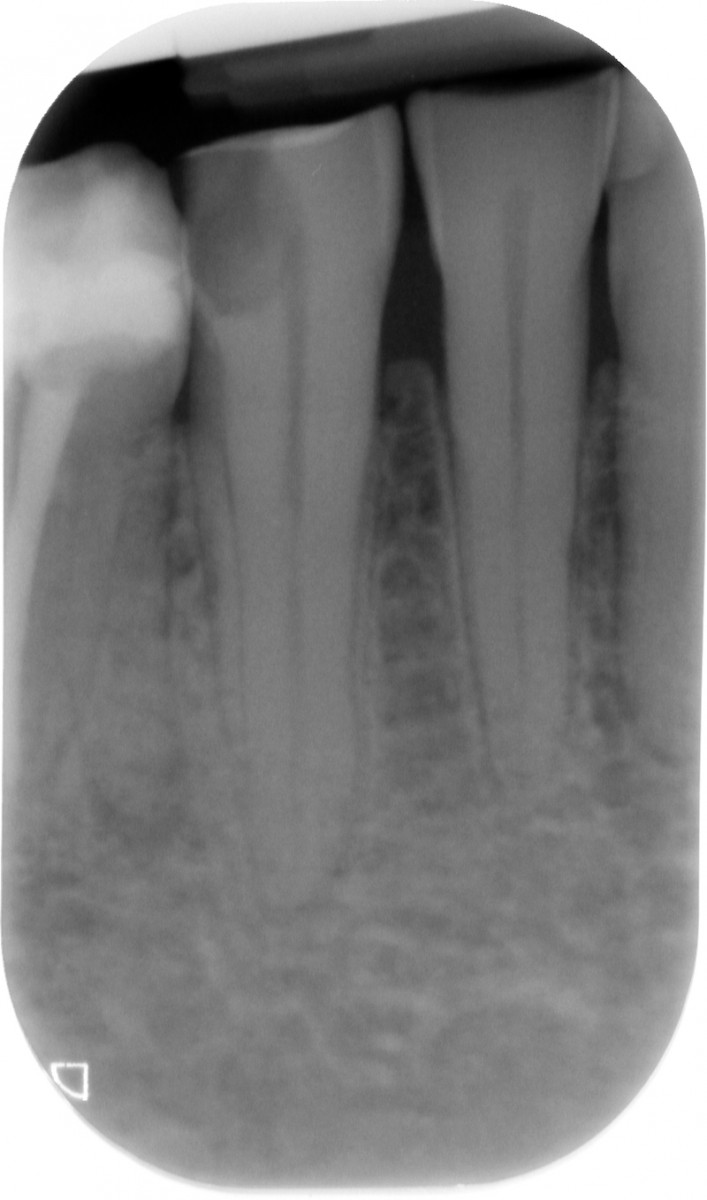

The gutta-percha point inserted into the root canal properly, adapting it to a size almost equal to the one employed to shape the apical terminus. Not wider, not smaller. Here are exposed a couple of cases made by shaping the root canal with a NiTi instrumentation technique and followed up for 9 to 12 months (Fig. 1-6).

It’s encouraging its easy handling and quite precise adaptation to the apical part of the root canal. The periapical healing, assessed by 2D-Rx, is considered satisfactory but further analysis and clinical studies related to these particular cements should be performed to confirm the first encouraging results.